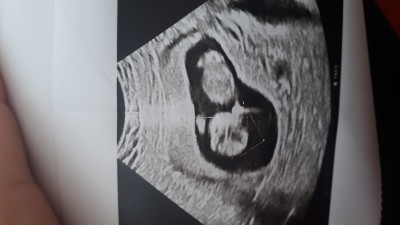

Tahminleri alayim :)

image

14 hafta 2 gunluk ama ultrason goruntusu 12 haftalik

Biri kız biri oglan bence:)

İki kese var gibi duruyor

Ilk defa siz soylediniz 2 kese ama doktor 2 kese demedi